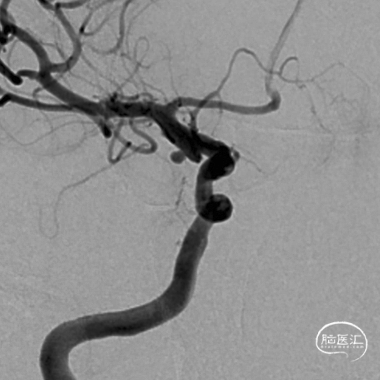

术前造影:后交通微小动脉瘤

后交通微小宽颈动脉瘤。

开颅风险较高,微小动脉瘤(宽颈),介入亦风险较高,又是颈内动脉(大流量高压力)后交通段动脉瘤,术中一旦破裂面临死亡的可能性较大。先预置支架导管,然后再置入动脉瘤内微导管,成蓝,必要时支架辅助栓塞动脉瘤。